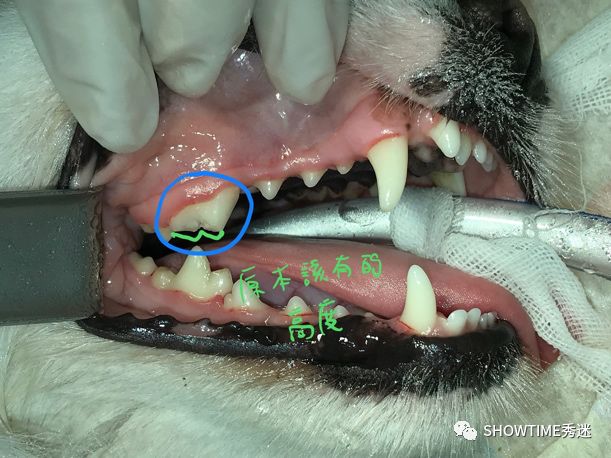

牙齿高度降低,仔细看可见裂痕!

主人讨论后,决定进行修补